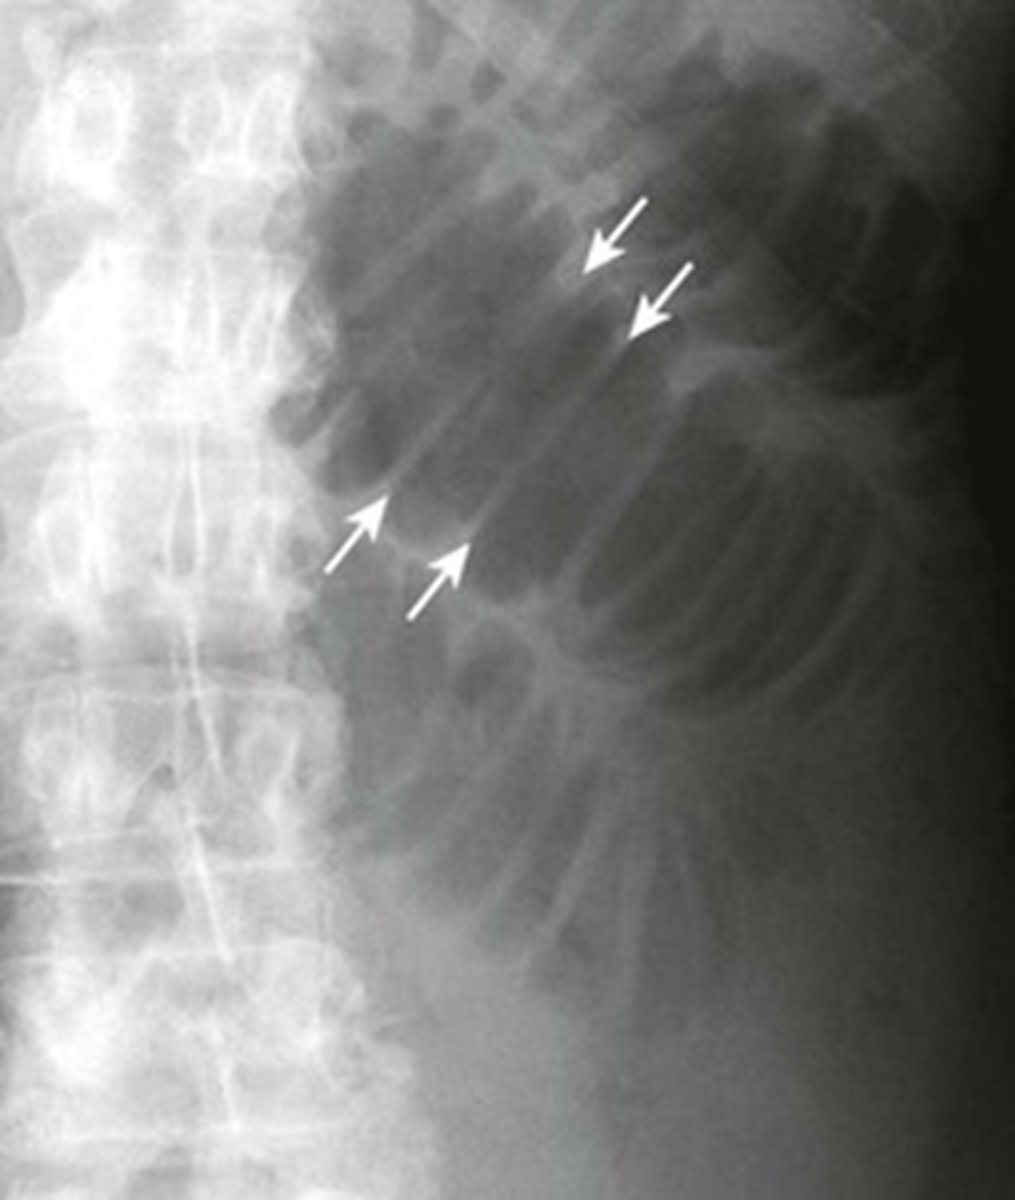

Pneumatosis - air in the abdominal wall.

WHITE ARROWS - RLQ demonstrating thin curvilinear lucency that parallels with the lumen of the adjacent bowel.

Appearance characteristic of gas in the bowel wall.

In infants the MC cause for this finding is necrotizing enterocolitis - a disease found mostly in premature infants in which the terminal ileum is most affected.

Pneumatosis intestinalis is pathognomonic for necrotizing enterocolitis in infants.